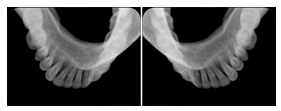

3. A dental provider wishes to capture a series of DICOM IO images for the patient’s dentition. The tooth morphology, teeth are divided into molars, premolars, canines and incisors, and a number of images for each jaw. The anatomic information was captured utilizing the triplet of schema. This standard code sequence is based on ISO 3950-2010, Dentistry - Designation system for teeth and areas of the oral cavity.

Every IO image should have anatomic information either through the primary or modifier sequence.

In most standard cases, images are oriented in structured layouts. These structured displays are useful to be shared between providers for reference purposes.

Table OO.1.1-1 shows structured display standard templates, where Viewset ID is based on the Japanese Society for Oral and Maxillofacial Radiology (JSOMR) classification provided by JIRA (Japan Medical Imaging and Radiological Systems Industries Association, www.jira-net.or.jp). Expected or typical teeth to be imaged location, region and designation codes are based on ISO 3950-2010, Dentistry - Designation system for teeth and areas of the oral cavity. For all the hanging protocols listed in OO.1.1-1, the value to use for Hanging Protocol Creator (0072,0008) is "JSOMR" and the value to use for Hanging Protocol Name (0072,0002) does not include "JSOMR" (e.g., "DL-S001A", not "JSOMR DL-S001A").